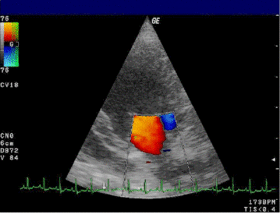

Doppler echocardiography is a procedure that uses ultrasound technology to examine the heart or blood vessels.[1] An echocardiogram uses high frequency sound waves to create an image of the heart while the use of Doppler technology allows determination of the speed and direction of blood flow by utilizing the Doppler effect.

An echocardiogram can, within certain limits, produce accurate assessment of the direction of blood flow and the velocity of blood and cardiac tissue at any arbitrary point using the Doppler effect. One of the limitations is that the ultrasound beam should be as parallel to the blood flow as possible. Velocity measurements allow assessment of cardiac valve areas and function, any abnormal communications between the left and right side of the heart, any leaking of blood through the valves (valvular regurgitation), calculation of the cardiac output and calculation of E/A ratio[2] (a measure of diastolic dysfunction). Contrast-enhanced ultrasound using gas-filled microbubble contrast media can be used to improve velocity or other flow-related medical measurements.